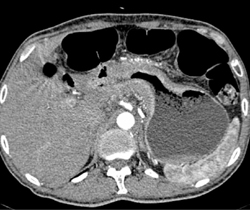

Gastric Adenocarcinoma